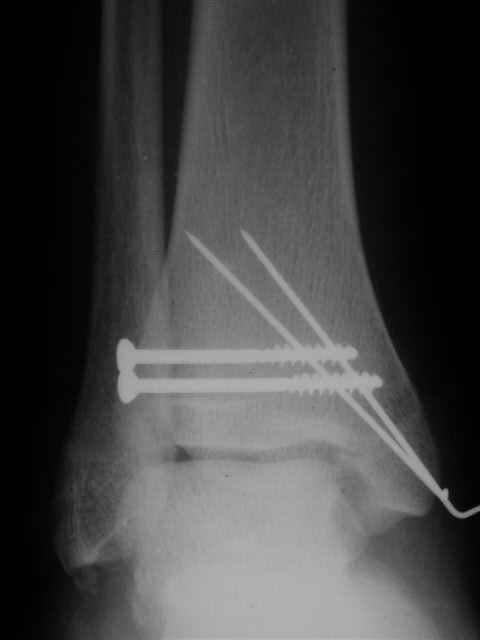

Уважаемый Иван,

Я предупреждал, что ничего сверхъестественного. Каюсь, что одна из спиц прошла несколько дальше, чем нужно было, но главное - перелом стабилизирован и больной работает суставом в полном объёме, несмотря на представленную раннее травму коленного сустава.